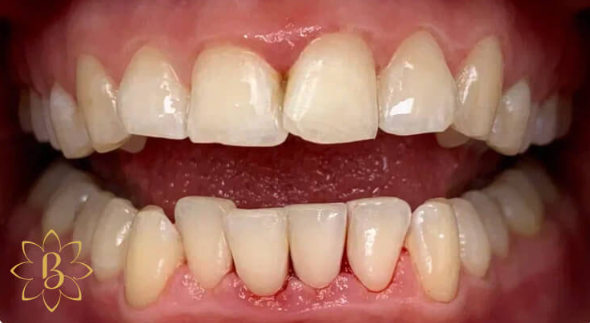

На странице представлено портфолио стоматологий Санкт-Петербурга с работами до и после профессиональной чистки зубов. В нашем портфолио собраны разные клинические случаи: от удаления незначительного налета до снятия массивного поддесневого камня. Здесь вы можете увидеть, как возвращается естественный цвет и внешний вид зубов после процедуры. Изучите результаты до и после чистки зубов, чтобы увидеть реальный эффект и выбрать клинику в Санкт-Петербурге, где профессиональная гигиена поможет вернуть зубам здоровый вид.